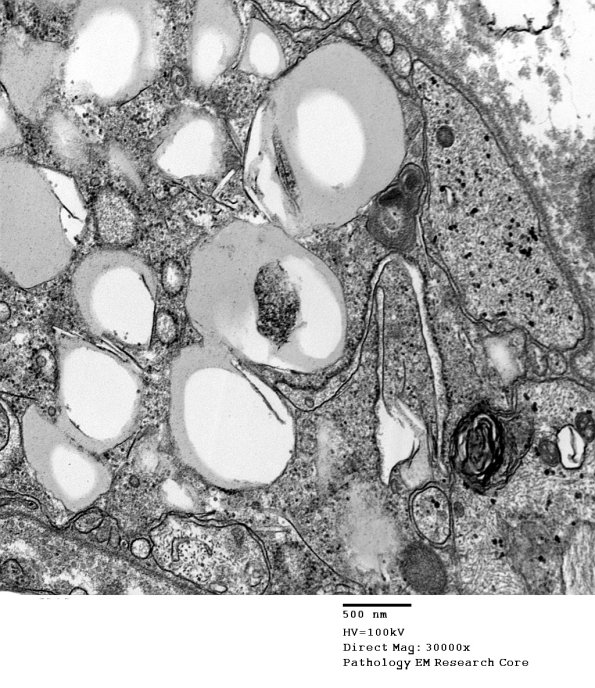

Higher magnification of the Schwann cell cytoplasm surrounded by a basement membrane.